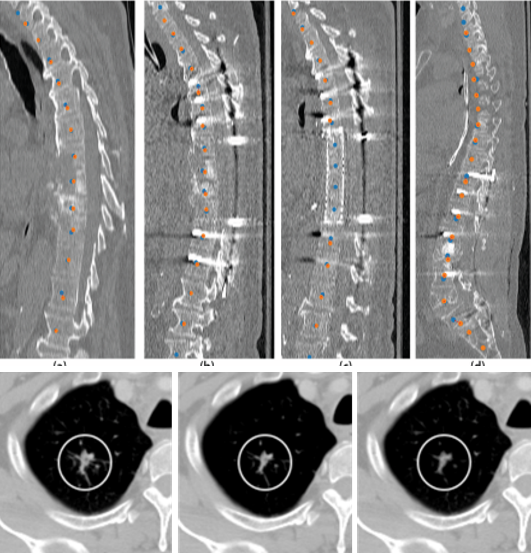

Medical imaging is now used extensively for accurate diagnosis, real-time intervention, and precision medicine. Our work has been focused on fast, high-resolution imaging augmented with functional and metabolic mapping. For example, dynamic 4D MRI under free breathing has been developed using PNCRNNs, with the reconstruction time as fast as 50 bin per second, offering substantial improvement of the image quality for dynamic golden-angle radial imaging of the abdomen. Novel imaging techniques have been developed for high-resolution whole-brain neurometabolic mapping, shedding light on in vivo molecular biomarkers for various brain diseases including stroke, brain tumor, and neurodegenerative disorders. A model-based deep learning architecture, referred to as MoDL-QSM, was developed with improved accuracy for quantifying tissue susceptibility for precise electrode implantation for deep-brain stimulation. To meet the demands for automated identification and localization of the vertebrae, pancreas, colon, lung nodules and other organs in low-dose CT, algorithms integrating local image details and global image patterns have been proposed. To extend the clinical use of nonlinear regression in medical imaging and image analysis, a deep negative correlation learning framework has been proposed to yield a deep regression of ensemble where each base model is both accurate and generalisable.

Vertebrae identification and localization

4.       Chen Y, Gao Y, Li K, Zhao L, and Zhao J. Vertebrae identification and localization utilizing fully convolutional networks and a hidden Markov model. IEEE Transactions on Medical Imaging, 2020, 39(2): 387-399.